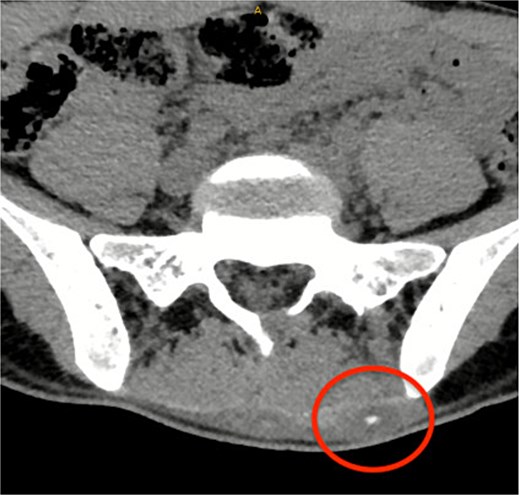

A CT lumbosacral spine was performed which demonstrated no spinal pathology but detected a left paraspinal calcified hematoma which was thought to be the cause of her symptoms and so was referred to the general surgeons (Fig. 1).

CT lumbosacral spine showed a left paraspinal calcified haematoma.